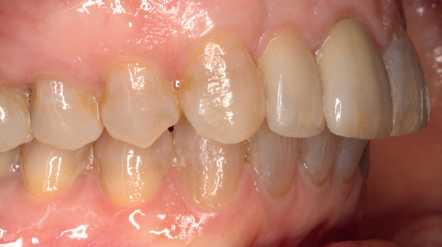

Cuatro meses después, se realiza un nuevo Cone-Beam dental para poder cuantificar la ganancia obtenida en anchura con el procedimiento regenerativo. Se observa en el corte seccional como se ha logrado una anchura de cresta de más de 7 mm y una regeneración completa del reborde alveolar, lo que permite la inserción de un nuevo implante dental en la posición adecuada (Figura 10). En la reentrada quirúrgica se constata la información del Cone-Beam con una integración total del material de injerto, tal como se muestra en las imágenes clínicas en el momento de la elevación del colgajo para la inserción del implante (Figuras 11 y 12). Se procede a la retirada del microtornillo y la colocación del implante, que se realiza mediante la compresión vestibular del injerto para ganar de esta manera aún más contorno en esta área (Figura 13). El implante se deja en una fase quirúrgica, con un pilar de cicatrización bajo que permita una localización posterior del mismo sin una cirugía agresiva del tejido blando para cuando se inicie la confección de la prótesis. El provisional sigue siendo una pieza en extensión desde el diente 1.1.

Tres meses después, se comienza con la fase protésica. El estado del tejido gingival es el correcto, aunque a nivel vestibular nos gustaría lograr un descenso del cenit del futuro diente, por lo que se planifica un injerto de conectivo que permita esta conformación de perfil de emergencia más adecuado. El caso se termina con coronas E max a nivel de 1.2 y 1.1, lográndose una sonrisa armónica y completa ente integrada en el resto de la sonrisa, en cuanto a color, emergencia y disposición de los márgenes gingivales (Figuras 14-15). La paciente continua en seguimien o durante años, mantenié dose la estabilidad de la rehabilitación llevada a cabo (Figura 16).